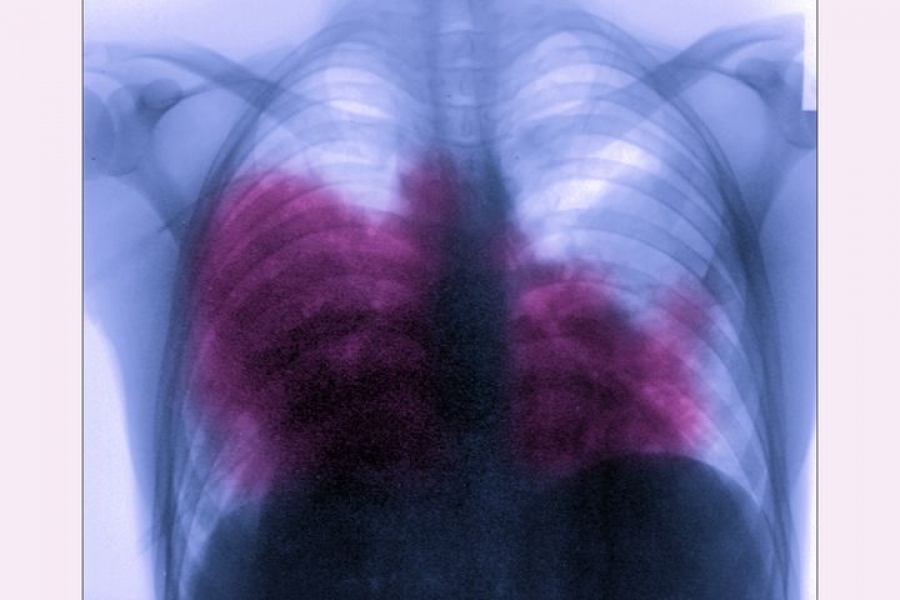

Τρεις άνθρωποι πέθαναν από τη νόσο των λεγεωνάριων στην πόλη Ζέσουφ της νοτιοανατολικής Πολωνίας, ενώ άλλοι 71 ασθενείς νοσηλεύονται εξαιτίας της επικίνδυνης λοίμωξης του αναπνευστικού, δήλωσε σήμερα στο Γαλλικό Πρακτορείο ένας εκπρόσωπος του τοπικού νοσοκομείου.

Οι τοπικές υπηρεσίες υγείας ανέφεραν ότι συνολικά 71 άτομα νοσηλεύονται εξαιτίας της λοίμωξης που προκαλείται από βακτηρίδια του γένους Legionella.

Η πηγή της μόλυνσης δεν είναι γνωστή και ο δήμος Ζέσουφ συγκάλεσε μια επιτροπή διαχείρισης κρίσεων.

Μια πρόσθετη απολύμανση του δικτύου ύδρευσης της πόλης είναι προγραμματισμένη να γίνει το Σαββατοκύριακο.

Τα αποτελέσματα των εξετάσεων δειγμάτων νερού που ελήφθησαν από διάφορες πηγές θα γίνουν γνωστά τη Δευτέρα.